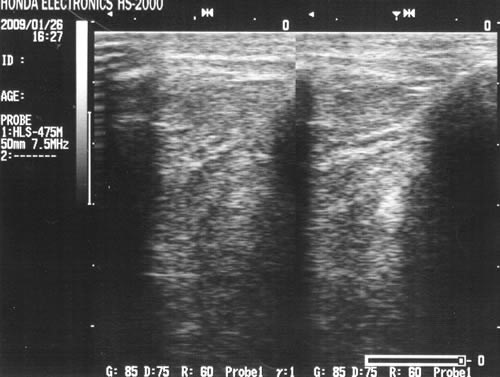

写真は断裂像です。(施術例1の患者様ではありません)

【 ACL長軸画像 】

左側が断裂像(患側)/右側が正常像(健側)。

ポイントは以下の2点。

・患側のACL中枢側が後方(画像上は下方向)に垂れている。

・ACLそのものの描出が不鮮明。